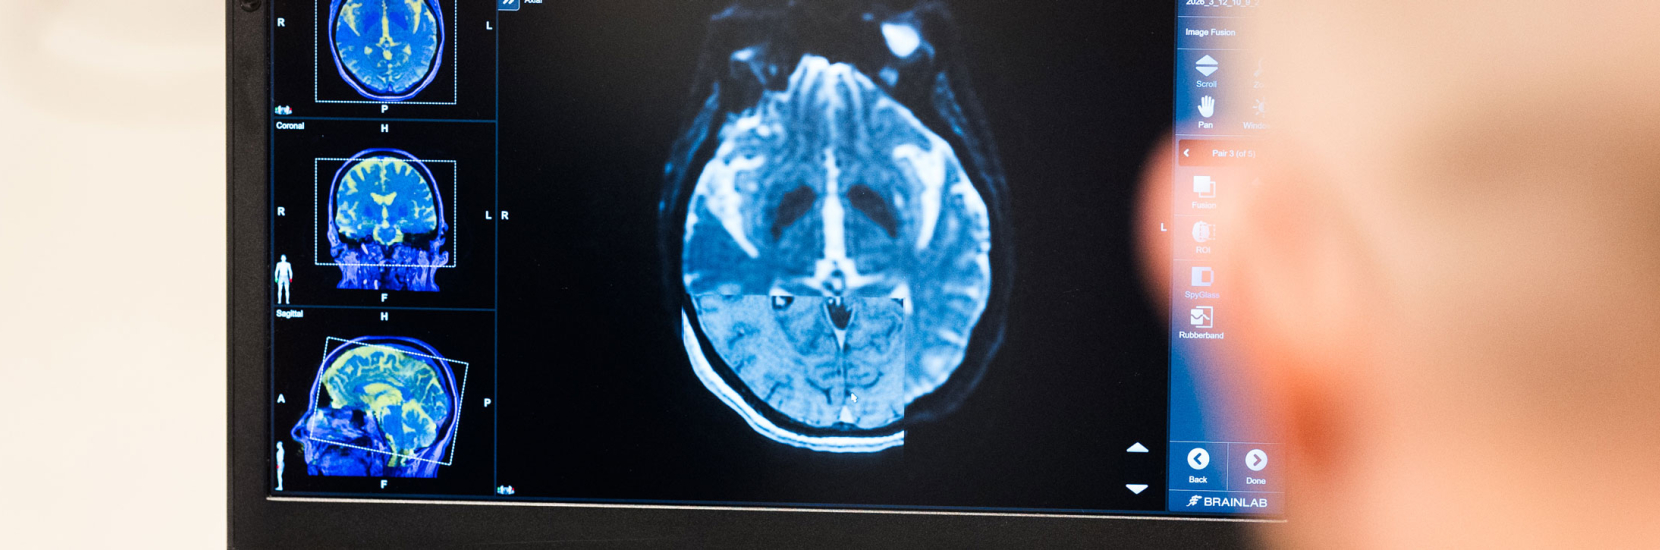

A particular focus was placed on modern technologies such as image-guided programming and wearable sensor systems for therapy monitoring.